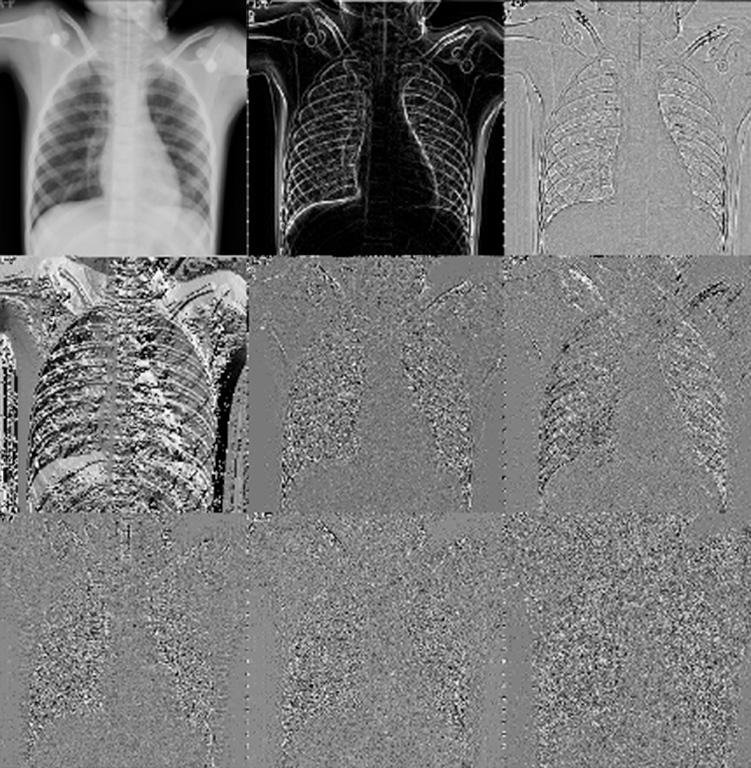

Similarly, the researchers participated in the presentation entitled, “The Authentication of Medical Images through a Hybrid Watermarking Method based on Hermite-Jigsaw-SVD,” where they discussed results from a robust method for watermarking medical images.

The doctors used the Steered Hermite transform (SHT), a spatial and frequency image decomposition technique inspired by the human vision system, to invisibly embed the watermark.

They also included singular value decomposition (SVD) in the proposal to obtain greater robustness of watermarks against attacks. They also used the Jigsaw transform to encrypt watermarks before embedding them in medical images. Finally, they used 40 X-ray images and the caduceus medical symbol as a watermark to evaluate the proposed watermarking method.

The results showed that the watermark is invisible to the human eye and is extracted without any loss of visual information. Furthermore, the marked medical images do not appear to have any significant visual alterations, preserving visual information for the patient’s diagnosis.

Furthermore, in tests involving attacks on a marked medical image, the results verified that the proposed method is robust and can stand up against common geometric and processing attacks (Gaussian noise, salt and pepper noise, median filter, JPEG compression, rotation, and translation), allowing the perceptible extraction of watermarks even in strong attacks where the marked medical image has lost a lot of information.